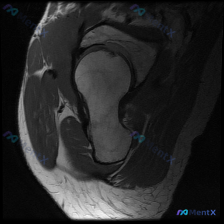

影像类型:髋关节MRI冠状位T1加权成像

主要表现:股骨头及股骨颈近端骨髓呈弥漫性T1低信号,与正常脂肪骨髓的高信号形成鲜明对比;髋臼顶轮廓清晰,关节间隙无明显狭窄,盂唇在T1序列上未见明确撕裂征象。

患者主诉提到了“盂唇病变”,但影像核心是骨髓信号异常。这个病例的诊断思路可能需要跳出局部关节病的范畴。大家觉得这个弥漫性T1低信号最可能的原因是什么?后续应该优先做哪些检查来明确诊断呢?